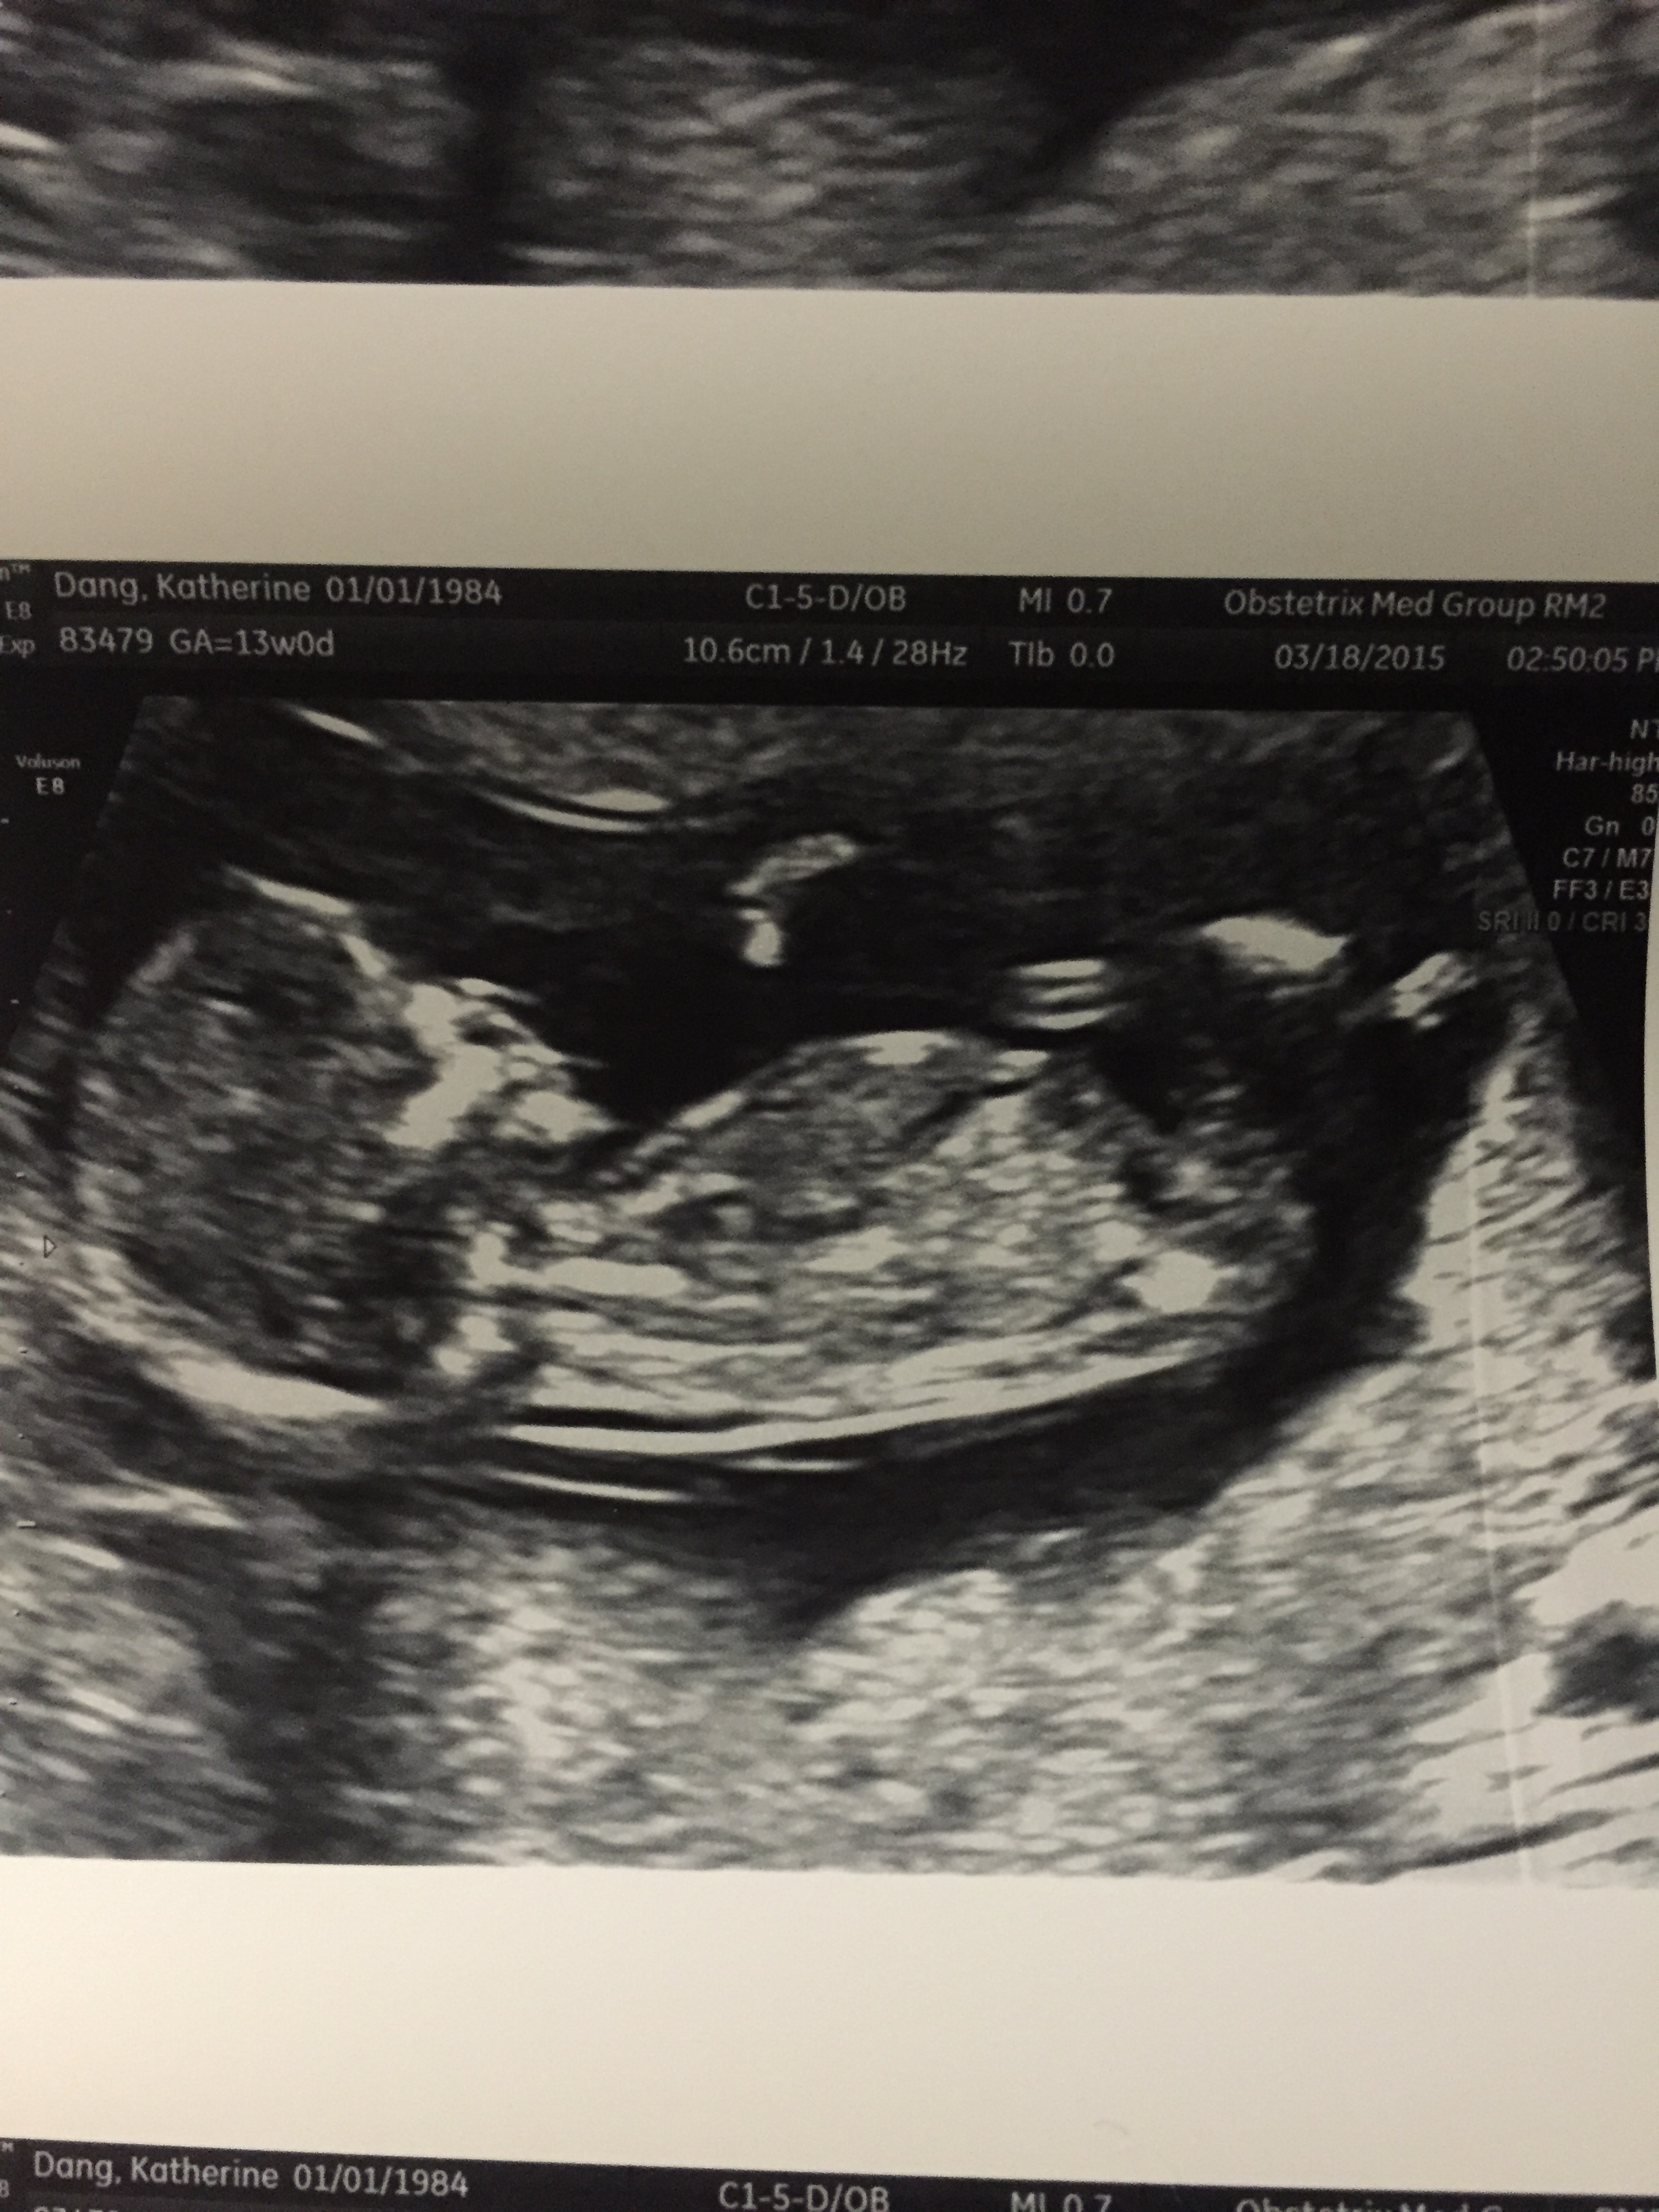

fe’ in more ways than one. This past weekend I saw my Grandma, Mom and little brother baptized, taking their first communion on Holy Saturday – the sacred space between Good Friday and Resurrection Sunday – a reminder to me that it is never too late for new life to emerge. About 15 weeks ago I came home to a cake that read, “Congrats Daddy.” The good news was kept a secret until a couple of weeks ago when we took Evangeline to Disneyland for the first time and made the announcement: G-money is going to be a big sister. Roughly 24 weeks from now we are going to have another Dang baby. New life, in it’s most literal sense. Between now and then, it is a threshold to enjoy, savor, and to prepare.

In our early conversations with doctors, we were given many options to consider in regards to CDH1 and pregnancy including early DNA testing, IVF, and other genetic options. From the beginning, Kate and I wanted to go about this pregnancy naturally. The bigger decision for us in the process is whether or not we want to know if our baby has the gene mutation now, or if we want to wait until much later in life. Sometimes it feels like the decision comes down to which will give us the least amount of anxiety: knowing our baby has CDH1 and not doing anything about it until after high school, or wondering whether or not our children have the genetic mutation until they are tested at 14? The benefit of knowing now also means knowing we do not have to worry if our children test negative for the gene mutation, and if they are positive, knowing how to prepare our children as they grow up with an awareness of CDH1. In the end, I do not have to work too hard to be reminded by Evangeline everyday that she is more than the sum of genetic coding. Moving forward, we are going to choose not to let CDH1 dictate our lives.